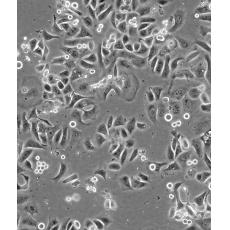

SK-BR-3 [SKBR-3;SKBR3]

產(chǎn)品名稱 SK-BR-3 [SKBR-3;SKBR3]

中文名稱 人乳腺腺癌細(xì)胞

生長(zhǎng)特性 adherent

形態(tài)特征 epithelial

細(xì)胞描述 he patient, a White, Caucasian female, age 43, blood type A+, had been treated with radiation, steroids, cytoxan and 5-fluorouracil.No virus particles.Ultrastructural features include microvilli and desmosomes, glycogen granules, large lysosomes, bundles of cytoplasmic fibrils.The SKBR- 3 cell line overexpresses the HER2/c-erb-2 gene product.